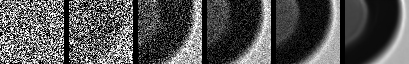

The visual quality of the generated samples from the fully trained models is illustrated in Figure 5. As can be seen, the synthesized images closely resemble real FIM images, capturing essential morphological features such as shape irregularities, texture, and transparency. Notably, the generated air bubble images preserve the circular and semi-translucent characteristics typically observed in real samples, while silicone oil droplets exhibit the distinct contour and scattering patterns that differentiate them from other SvP types. These qualitative results suggest that our diffusion models effectively learns the underlying distribution of each particle type, despite the low data regime.

3.3 Misclassified Protein Particles

In Figure 6, we present several SvP images labeled as ’protein particles’ that are consistently misclassified by our models as silicone oil droplets or air bubbles. Upon initial inspection, many of these particles appear spherical or transparent which are visual traits more commonly associated with silicone oil or air bubbles than protein aggregates. After expert review, we conclude that several of these images are indeed more likely to be silicone oil droplets or air bubbles, indicating possible inaccuracies in the original ground truth labels. In other cases, particularly for the blurry or amorphous particles, the true identity remains uncertain, as such morphology could correspond to protein particles. These observations demonstrate that our model is highly sensitive to subtle morphological differences and, in some cases, may even outperform the original annotations by correctly reclassifying mislabeled examples.